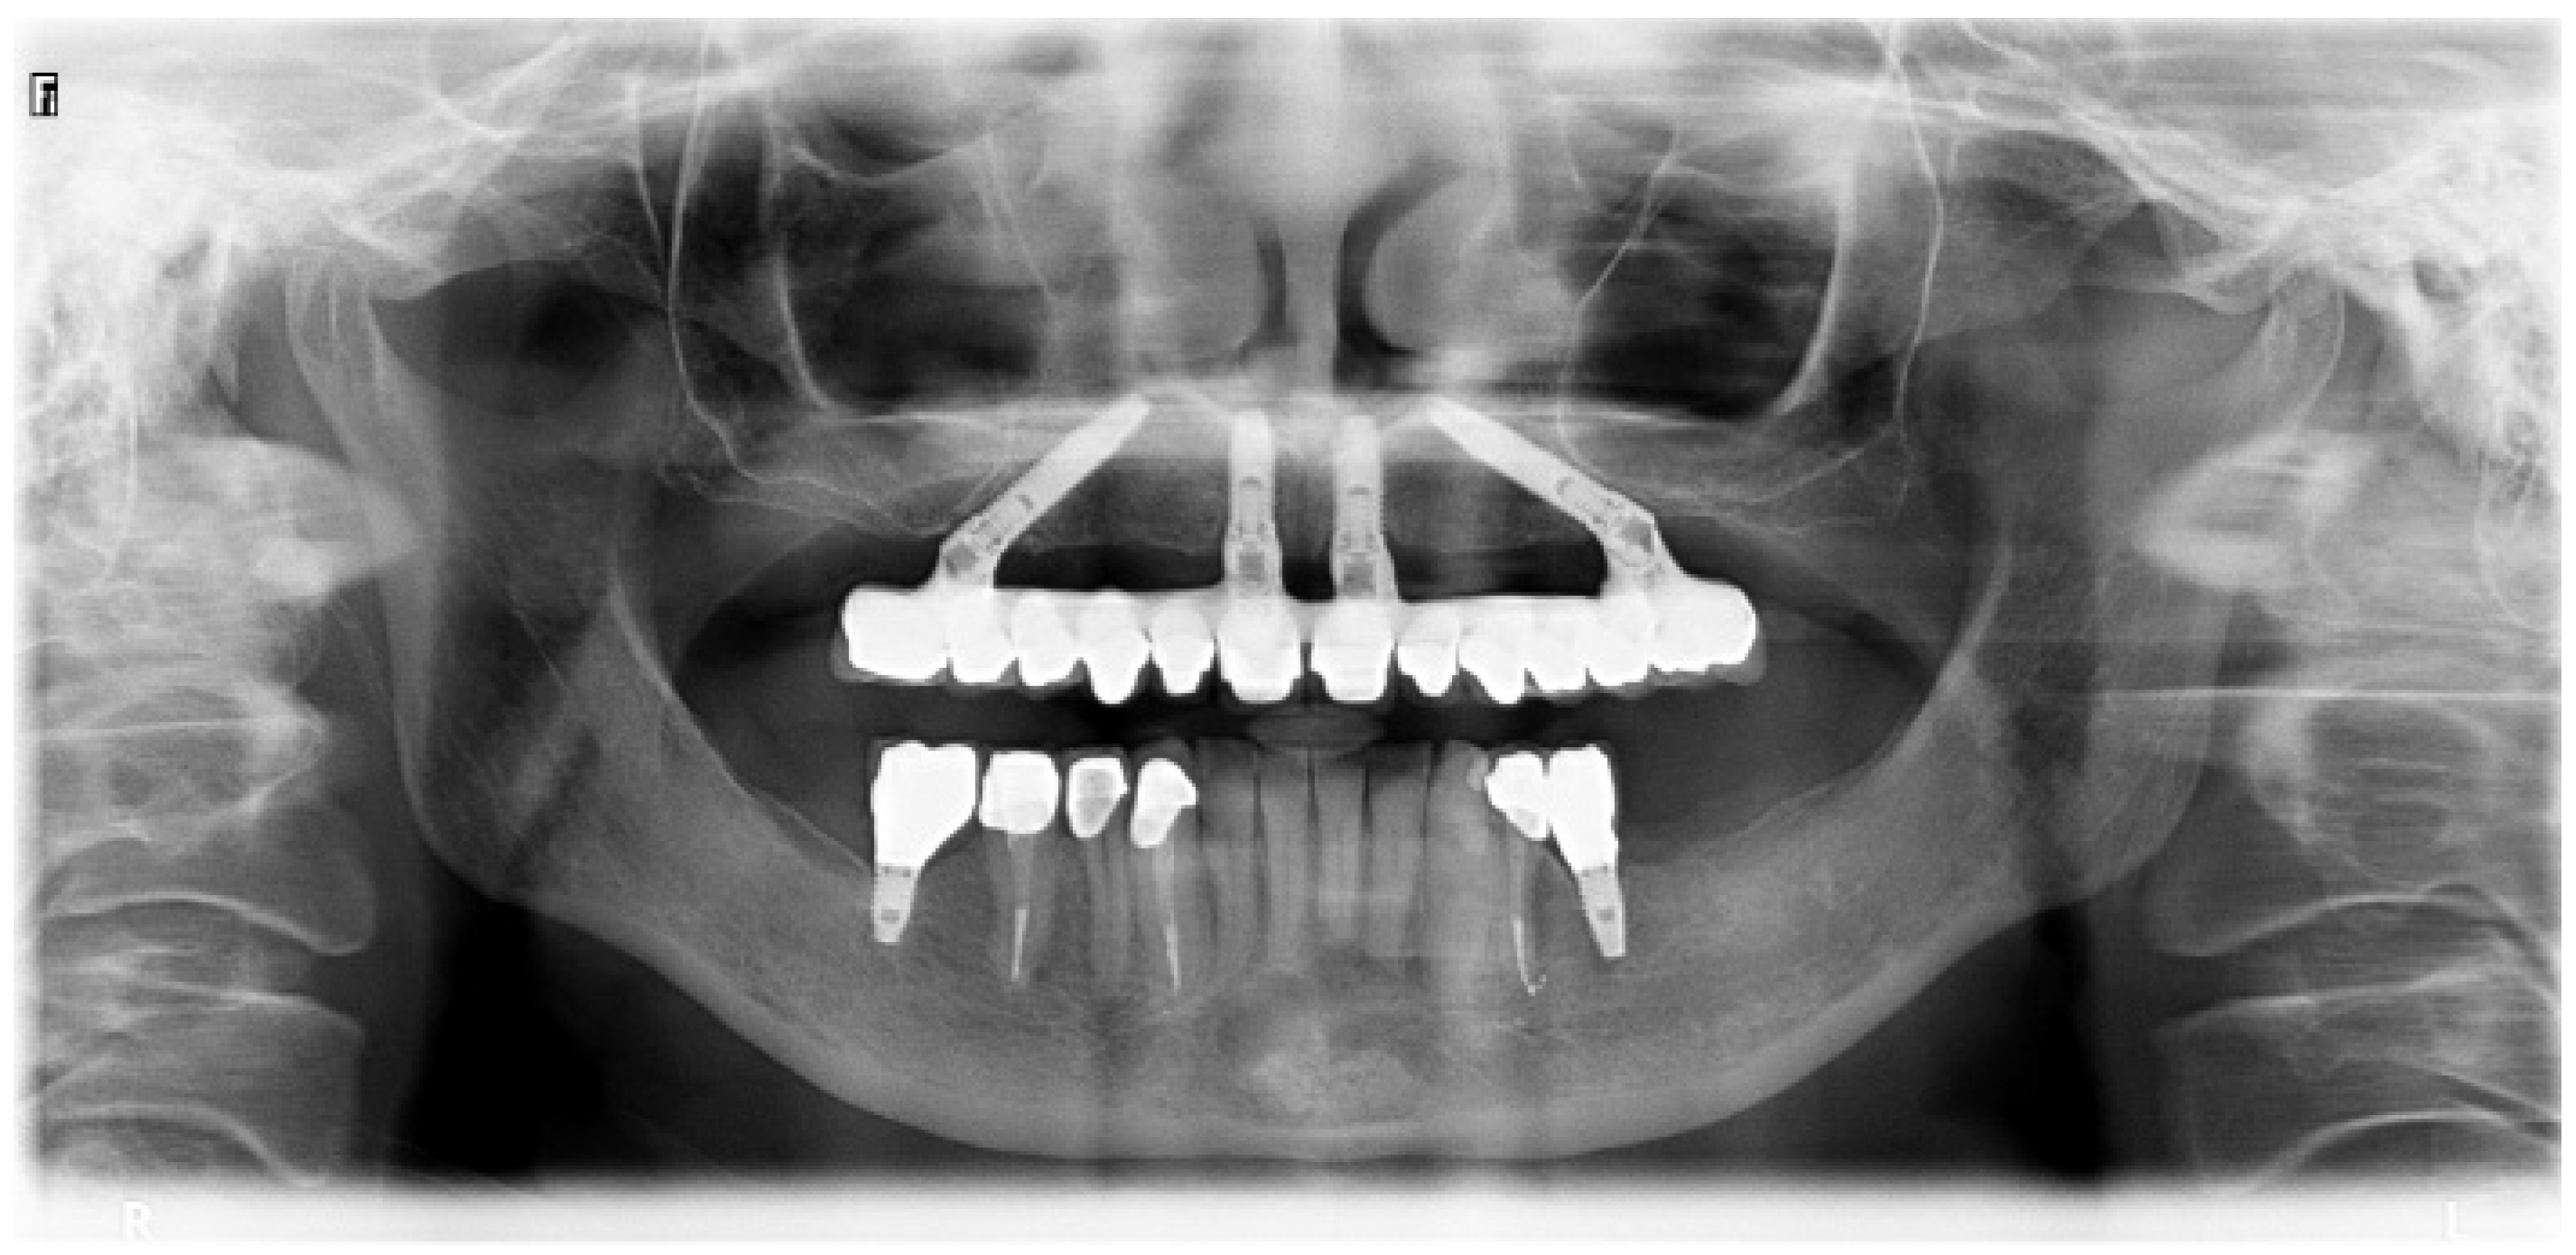

In the present study, short implants measuring 7 mm in length were used. In total, 217 short implants (NobelSpeedy Shorty, Nobel Biocare AB) were placed (21 in the maxilla and 196 in the mandible), out of the total of 157 rehabilitations (20 in the maxilla and 137 in the mandible), with 141 single teeth (16 in the maxilla and 125 in the mandible) and 16 partially fixed prostheses (4 in the maxilla and 12 in the mandible). A case illustration is presented in Figure 3, Figure 4 and Figure 5.

Figure 4. Follow-up periapical radiograph illustrative of the 5-year follow-up of the short implant (4th quadrant).